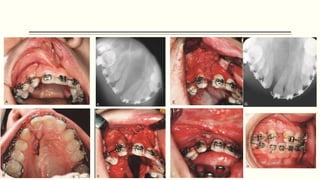

Alveolar Cleft Grafts

 Timing of graft procedure; the patient is between ages 6 and 10 years, a major portion of

maxillary growth has occurred, and the alveolar cleft surgery should not adversely affect

the future growth of the maxilla.

 Surgical procedure.

 Intact mucoperiosteal flaps on each side must cover bone grafts placed into the alveolar

cleft.

 The bone placed into the alveolar cleft is usually obtained from the patient’s ilium or

cranium; however, some surgeons are using allogeneic bone (i.e., homologous bone from

another individual) and recently bone morphogenetic proteins (BMP)

 The grafts are made into a particulate consistency and are packed into the defect once

the nasal and palatal mucosa has been closed.

 The labial mucosa is then closed over the bone graft.